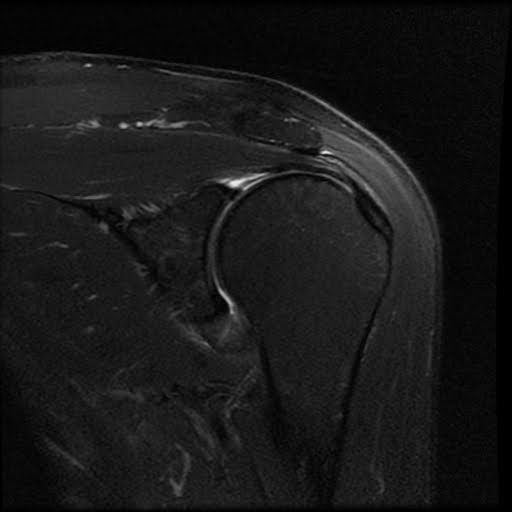

Adhesive capsulitis shoulder Image

from radiopaedia.org